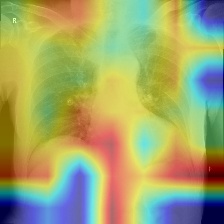

We produce localization maps by computing Ablation-CAMs for our models, applied to over 100 images from the COVIDx test split. These maps highlight image regions deemed important by the model for classifications. Figures 2(a) and 2(b) show three example COVID-positive images and localization maps computed on the Swin-B model (200-epoch). Figure 2(c) shows corresponding maps produced by the ResNet-50 baseline model on the same images.

The localization maps produced by Swin Transformers highlight the lung area, successfully focusing on the ground glass pattern, consolidation and peripheral linear opacities used by human doctors for diagnosis (Cleverley et al., 2020). In contrast, maps produced by the ResNet-50 are less successful, highlighting irrelevant areas such as shoulders and arms, sometimes missing the lungs entirely.